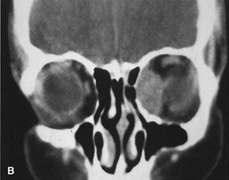

Lateral orbitotomy provides excellent access to deep lesions in the subperiosteal, peripheral, or intraconal space lateral to the optic nerve (Fig. 8A, B).

Fig. 8. Coronal (A) and axial (B) views in an illustration of areas (shaded) amenable to lateral orbitotomy.